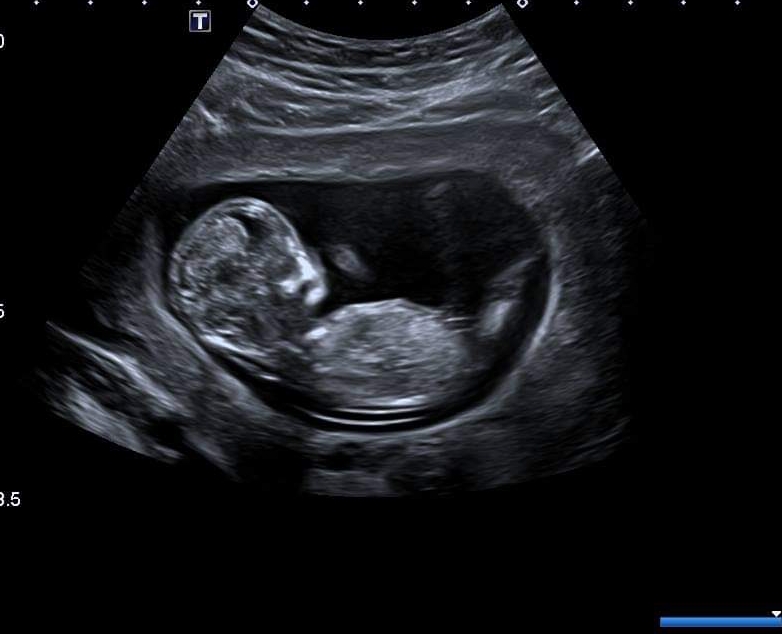

Would anyone be kind enough to guess the gender of my baby at 12+1? I'm not sure if there's a nub but I've included 3 pics so hopefully there's some clues.

Possibly a boy as there looks to be some stacking on picture 1. I’m not great at nun theory though. Picture 3 alone looks more girly as can’t see the stacking but I’m leaning blue

Thanks so much! Definitely not a clear one, even the skull looks girly in some pics and boy in others